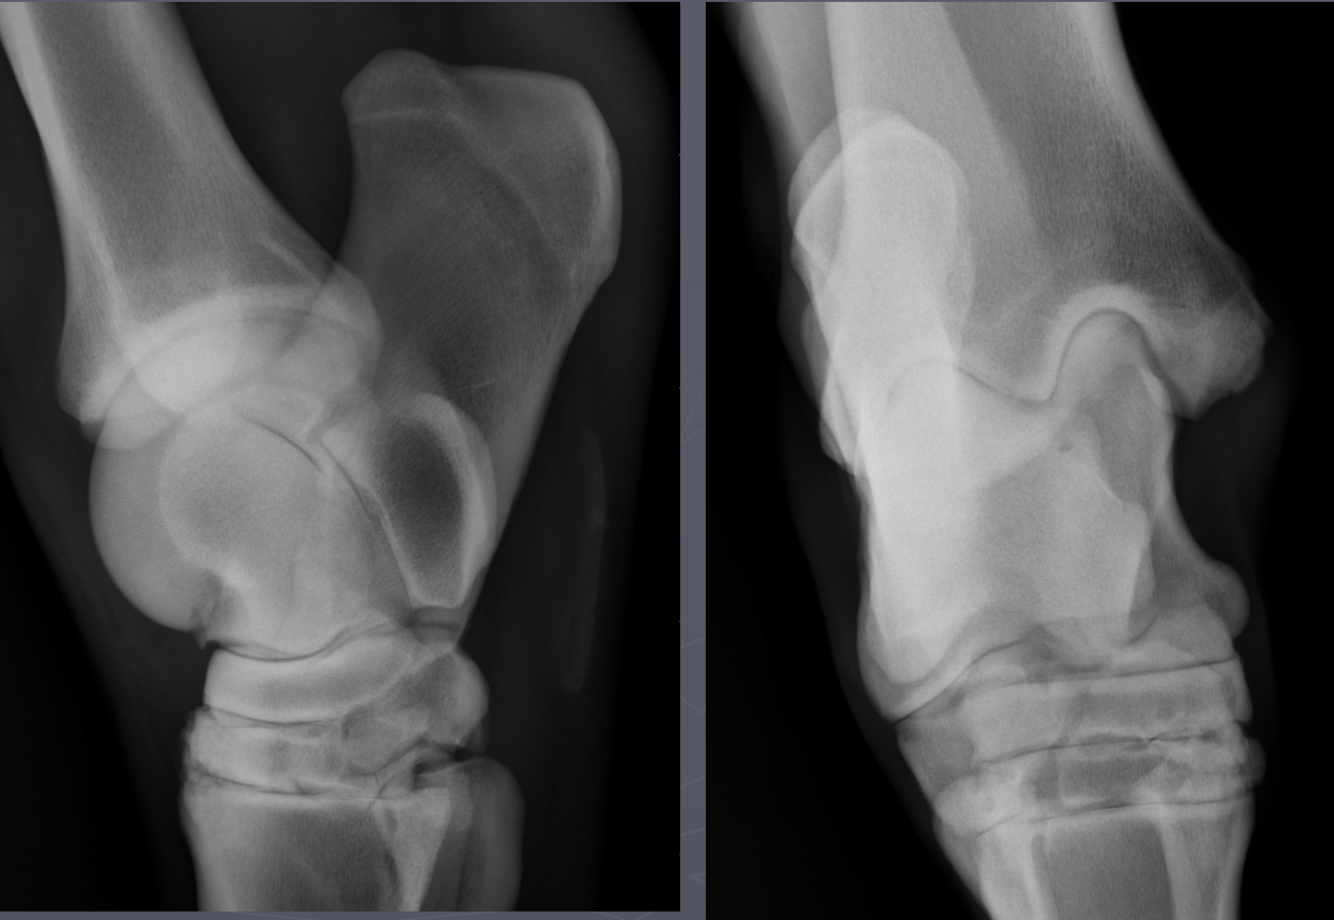

What is shown in these images?

Left: osseous cyst-like lesion, lysis, DJD, and fragmentation Right: osseous cyst-like lesion, flattening of condyle, DJD (less so than left image)